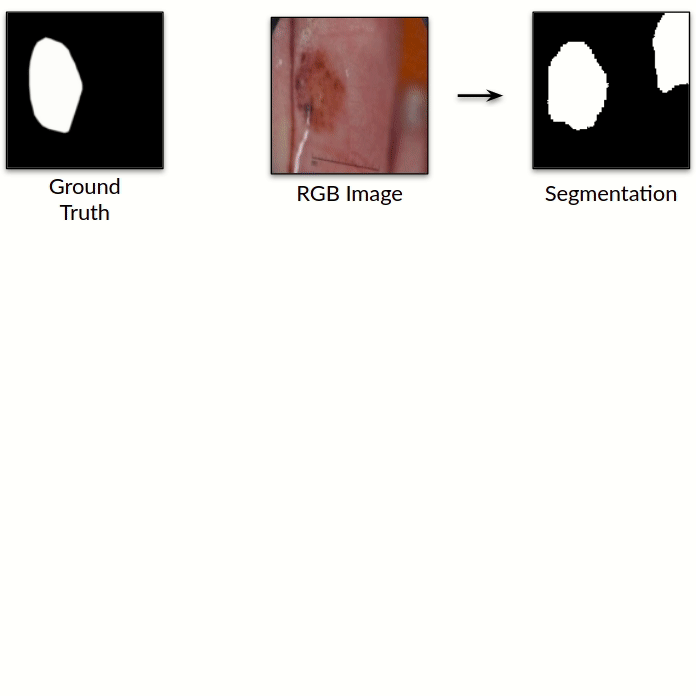

Improved Inference via Deep Input Transfer

Saeid Asgari Taghanaki, Kumar Abhishek, Ghassan Hamarneh

International Conference on Medical Image Computing and Computer Assisted Intervention (MICCAI), 2019

(Early Accept)

We propose an input image transformation technique that relies on the gradients of a trained segmentation network to transform the images for improved segmentation performance. [Abstract] [BibTeX]

Although numerous improvements have been made in the field of image segmentation using convolutional neural networks, the majority of these improvements rely on training with larger datasets, model architecture modifications, novel loss functions, and better optimizers. In this paper, we propose a new segmentation performance boosting paradigm that relies on optimally modifying the network's input instead of the network itself. In particular, we leverage the gradients of a trained segmentation network with respect to the input to transfer it to a space where the segmentation accuracy improves. We test the proposed method on three publicly available medical image segmentation datasets: the ISIC 2017 Skin Lesion Segmentation dataset, the Shenzhen Chest X-Ray dataset, and the CVC-ColonDB dataset, for which our method achieves improvements of 5.8%, 0.5%, and 4.8% in the average Dice scores, respectively.